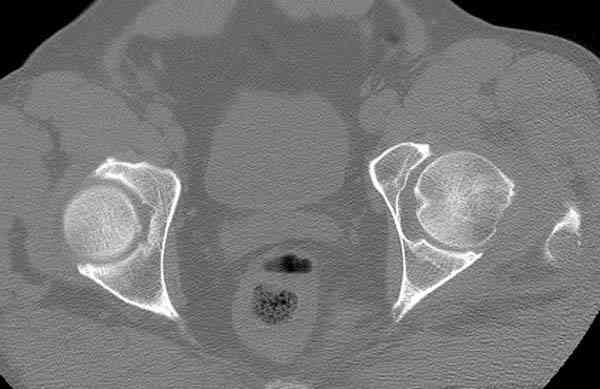

Кроме обязательных ренгенологических снимков тазобедренного сустава, при подозрении на перелом шейки рекомендуем Компьютерную Томографию.

Года два назад в ОТА из группы Торнетта было доложено о "missed femoral neck fractures" даже после КТ исследования.

Здесь представлены снимки больного 65 лет, поступившего с диагнозом перелом

бедра после автоаварии.

В первый же день произведено антеградное штифтованием DePuy Trochanteric Nail.

На второй день (7) обнаружен пропущенный перелом,

сделаны Компьютерная Томограмма

и проведены шурурпы через и спереди штифта без удаления.